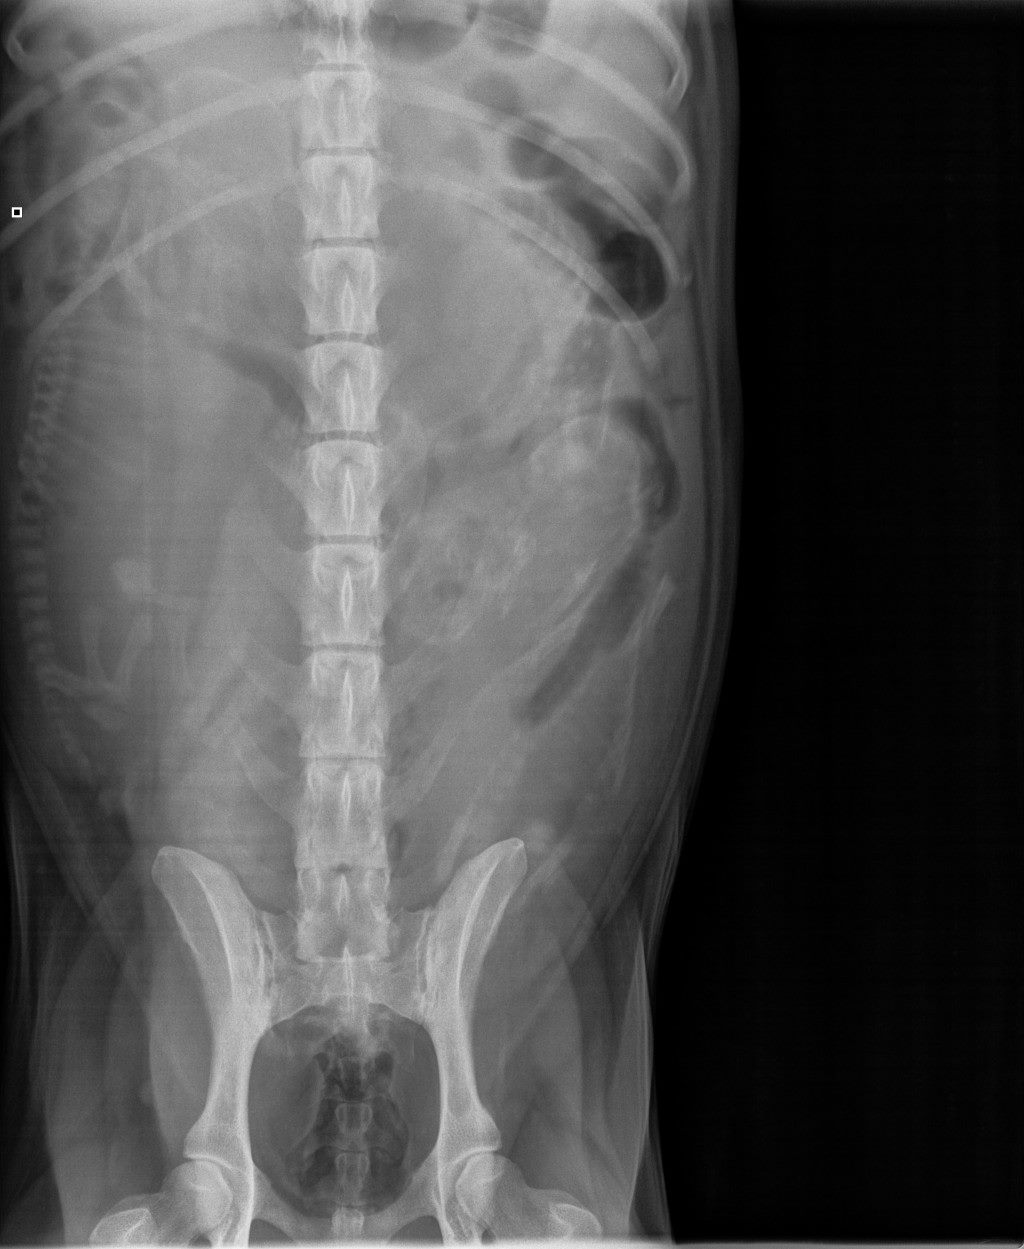

Lonkat |

A/A |

terveet |

B/B |

Kyynärpäät |

0/0 |

*) 6 koiran (muut paitsi Pikimusta ja Parfyymi) luustokuvaukset tehtiin 19.3.10 ell Kari Ventelän toimesta.

Kuvatuissa nivelissä ja selkärangassa ei havaittu muutoksia.